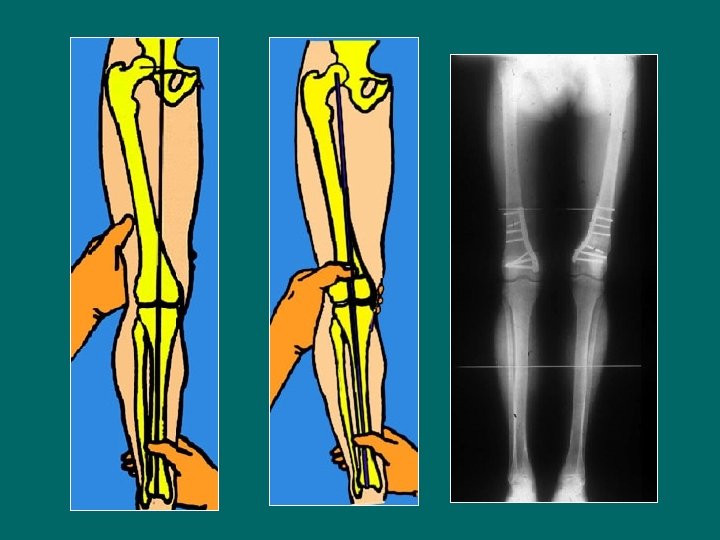

1/ Ostéotomie de fermeture interne du fémur Lame-plaque AO Vérification radioscopique perop de l’alignement du fémur et du tibia

Autres procédés d’ostéosynthèse Ouverture Fermeture